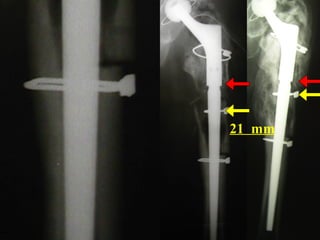

Paprosky

3-B (4)

Vanc. B - 3

21 mm

Subsidence

=

NO

LOOSENING

1999

1988

T 3 STEM